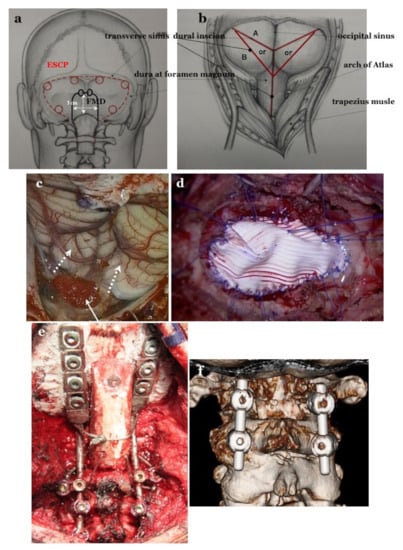

2.4.1. Foramen Magnum Decompression (FMD) for CM-I Type B and CM-Borderline

2.4.2. Expansive Suboccipital Cranioplasty (ECSP) for CM-I Type C

2.4.3. CCF for CM-I with CCJ Instability